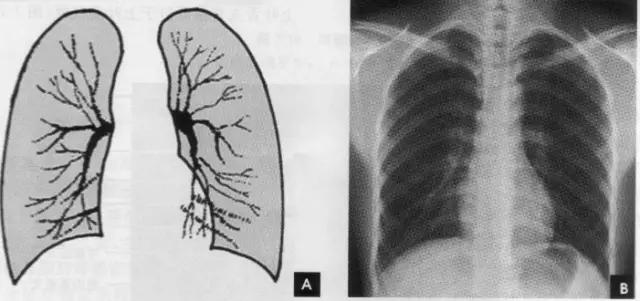

(七)肺纹理 肺纹理为自肺门向肺野呈放射状分布的树枝状阴影,它主要是肺动脉的投影,肺静脉、支气管和淋巴管也参与形成。平片可显示肺纹理的多少,粗细.分布,有无扭曲、变形与移位等。肺纹理由肺门向外围延伸,逐渐变细,至肺野外带渐细小而稀少,距侧胸壁内缘约1cm范围内的肺野基本无肺纹理可见(图下图)。